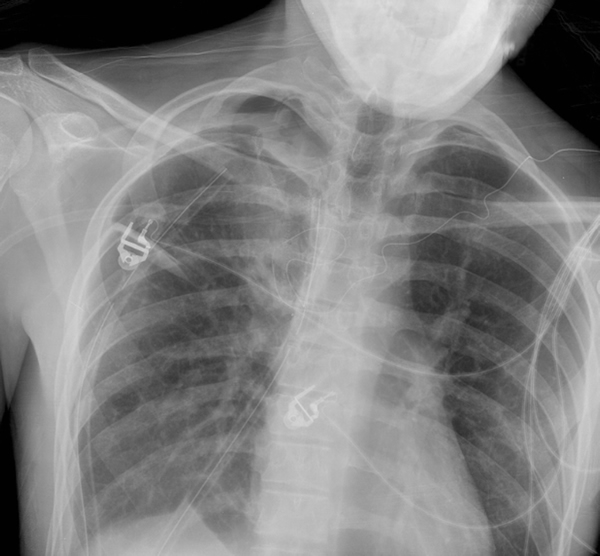

Patients who have had a second episode of spontaneous pneumothorax are those most likely to be considered for thoracoscopic pleurectomy and apical blebectomy. However, patients with a first episode of spontaneous pneumothorax who have a prolonged air leak (greater than 72 hours), incomplete expansion of the lung (Figure 1), bilateral pneumothoraces, associated hemothorax, tension pneumothorax (Figure 2), or a bleb on their CT scan (Figure 3) should be offered surgery at the time of the first occurrence [1]. Patients who have had a spontaneous pneumothorax and whose occupation places them at risk for a second episode or places them in a situation where medical intervention is not readily accessible should be considered for surgery. Therefore divers, pilots, submarine personnel, and those that work or live in the wilderness or space are suitable patients [1].

| Figure 1: Chest x-ray showing incomplete expansion of lung after chest tube placement. | Figure 2: Chest x-ray showing tension pneumothorax with mediastinal shift. | Figure 3: CT Scan showing apical bleb. |